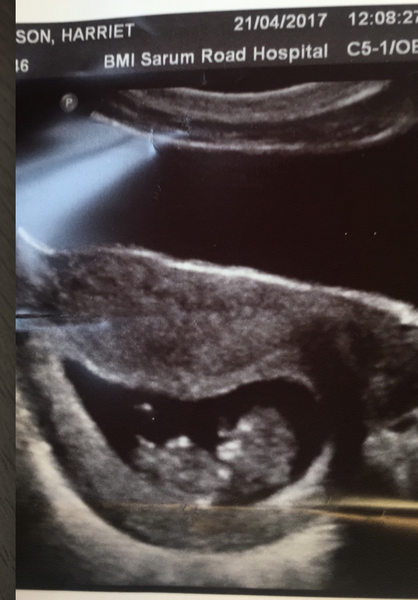

Hello everyone, had an early reassurance scan today and am measuring in line with my LMP just a day or two behind (they said 10+5 when they scanned but put 10+4 on my notes, hey ho) so have an EDD of 13th of November. I cannot believe there was an actual baby shaped little thing inside. Couldn't stop crying. I've now finally called my drs to organise booking in! X